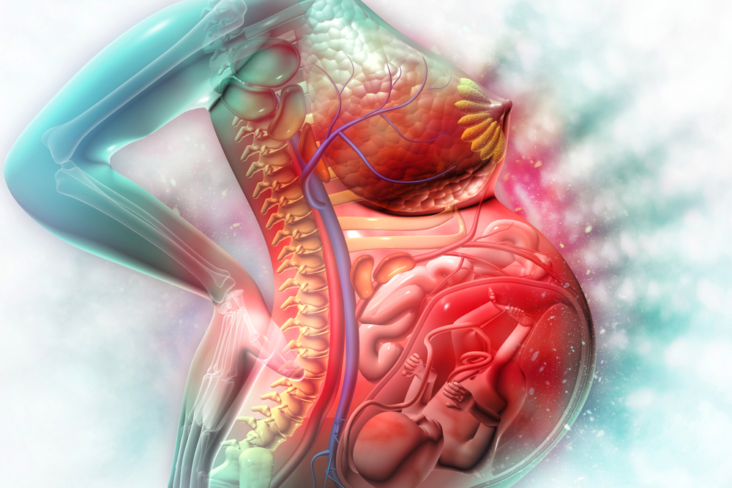

Symptômes des lésions de la moelle épinière et des vertèbres

Si la moelle épinière est lésée, les nerfs se trouvant au site et en dessous du site de la lésion fonctionnent mal, ce qui se traduit par une perte de contrôle musculaire et une perte de sensation.

Quelles sont les conséquences d’une lésion de la moelle épinière ?

Une lésion de la moelle épinière peut causer une paraplégie (paralysie des membres inférieurs) ou une tétraplégie (paralysie des membres inférieurs et supérieurs) entraînant des pertes sensitives et motrices mais aussi des troubles génito-sphinctériens.

Quels sont les risques liés à une compression de la moelle épinière ?

Les lésions qui compriment la moelle épinière peuvent également comprimer les racines nerveuses ou, de façon rare, freiner la vascularisation artérielle médullaire, provoquant un infarctus médullaire.